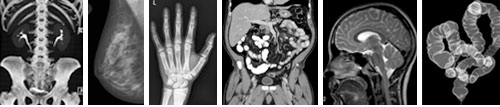

C. 高清核磁共振扫描,德国著名专家分析解读。

-全身核磁共振标准扫描

-下腹部精确核磁共振扫描

-脊椎精确核磁共振扫描

-脑部精确核磁共振扫描

-心肺及血管精确核磁扫描

体检中心拥有巴伐利亚州唯一一台3特斯拉高场磁共振成像机(MRI)。以及最新的64层CT系统等全球尖端医疗设备,确保以最小的辐射获得最佳的图像质量,从而为您提供最高的诊断准确度。